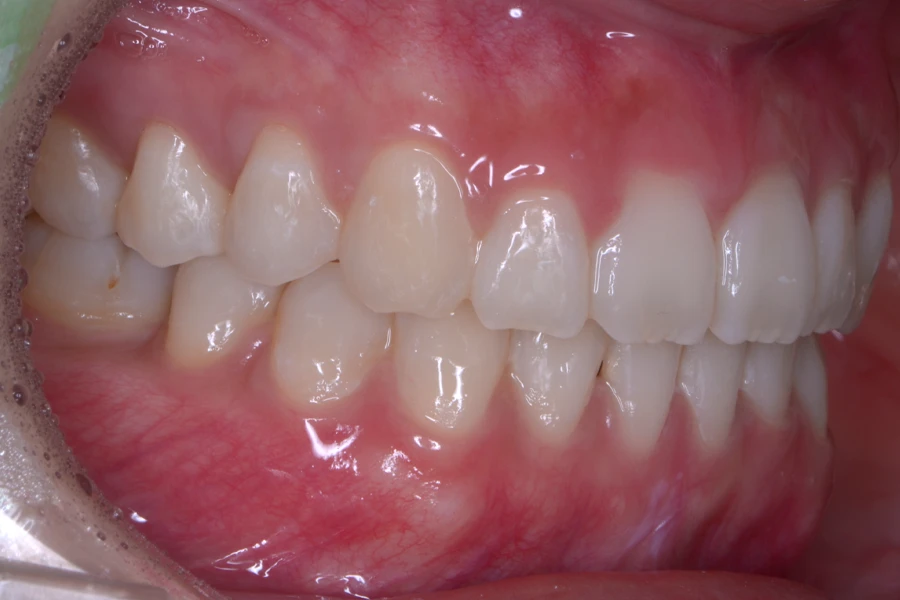

治療前

主訴 結婚式までに前歯を綺麗に整えたい

期間 10か月

費用 40万円(別途調整料)

デンタルローン80回 ¥5,800/月

治療内容 上下顎ラビアル矯正(表側矯正)

治療に伴うリスク 後戻り